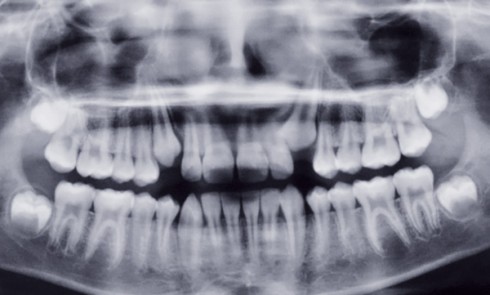

Article réservé à nos abonnés Prise en charge prothétique d’un enfant atteint d’une dysplasie ectodermique hypohidrotique

La dysplasie ectodermique est une génodermatose héréditaire liée au chromosome X qui comprend toute une série d’anomalies du développement et...